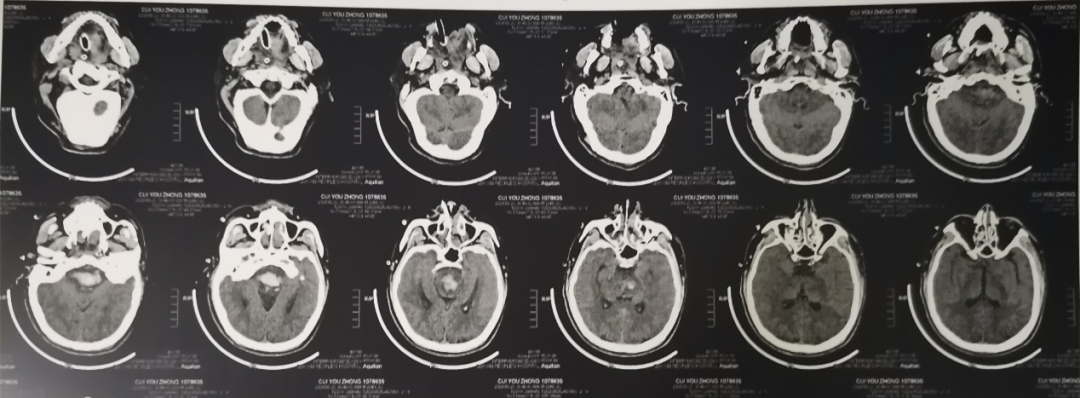

脑干:桥脑出血——相信很多医生看到这几个字,都要不免叹息一声,因为脑干出血是原发性脑出血中最为危重的类型。“脑干虽小,却是各种神经传导束的必经之地,即使微小的病变也可引起较为严重的后果。崔某脑干出血量达到5ml,呈持续性植物状态。”成都顾连锦宸康复医院神经康复科主任江玥解释道。

刚入院时,崔大哥呈植物状态,睁眼昏迷,仅对威胁有眨眼反应,气管切开、留置胃管、肺部和尿路感染、营养不良等。李女士的希望很简单,就是丈夫能够醒来并回应自己。我院神经康复团队对崔大哥的疾病、身体结构和功能、意识内容和水平、神经电生理进行精确评估后,制定了针对性康复方案。